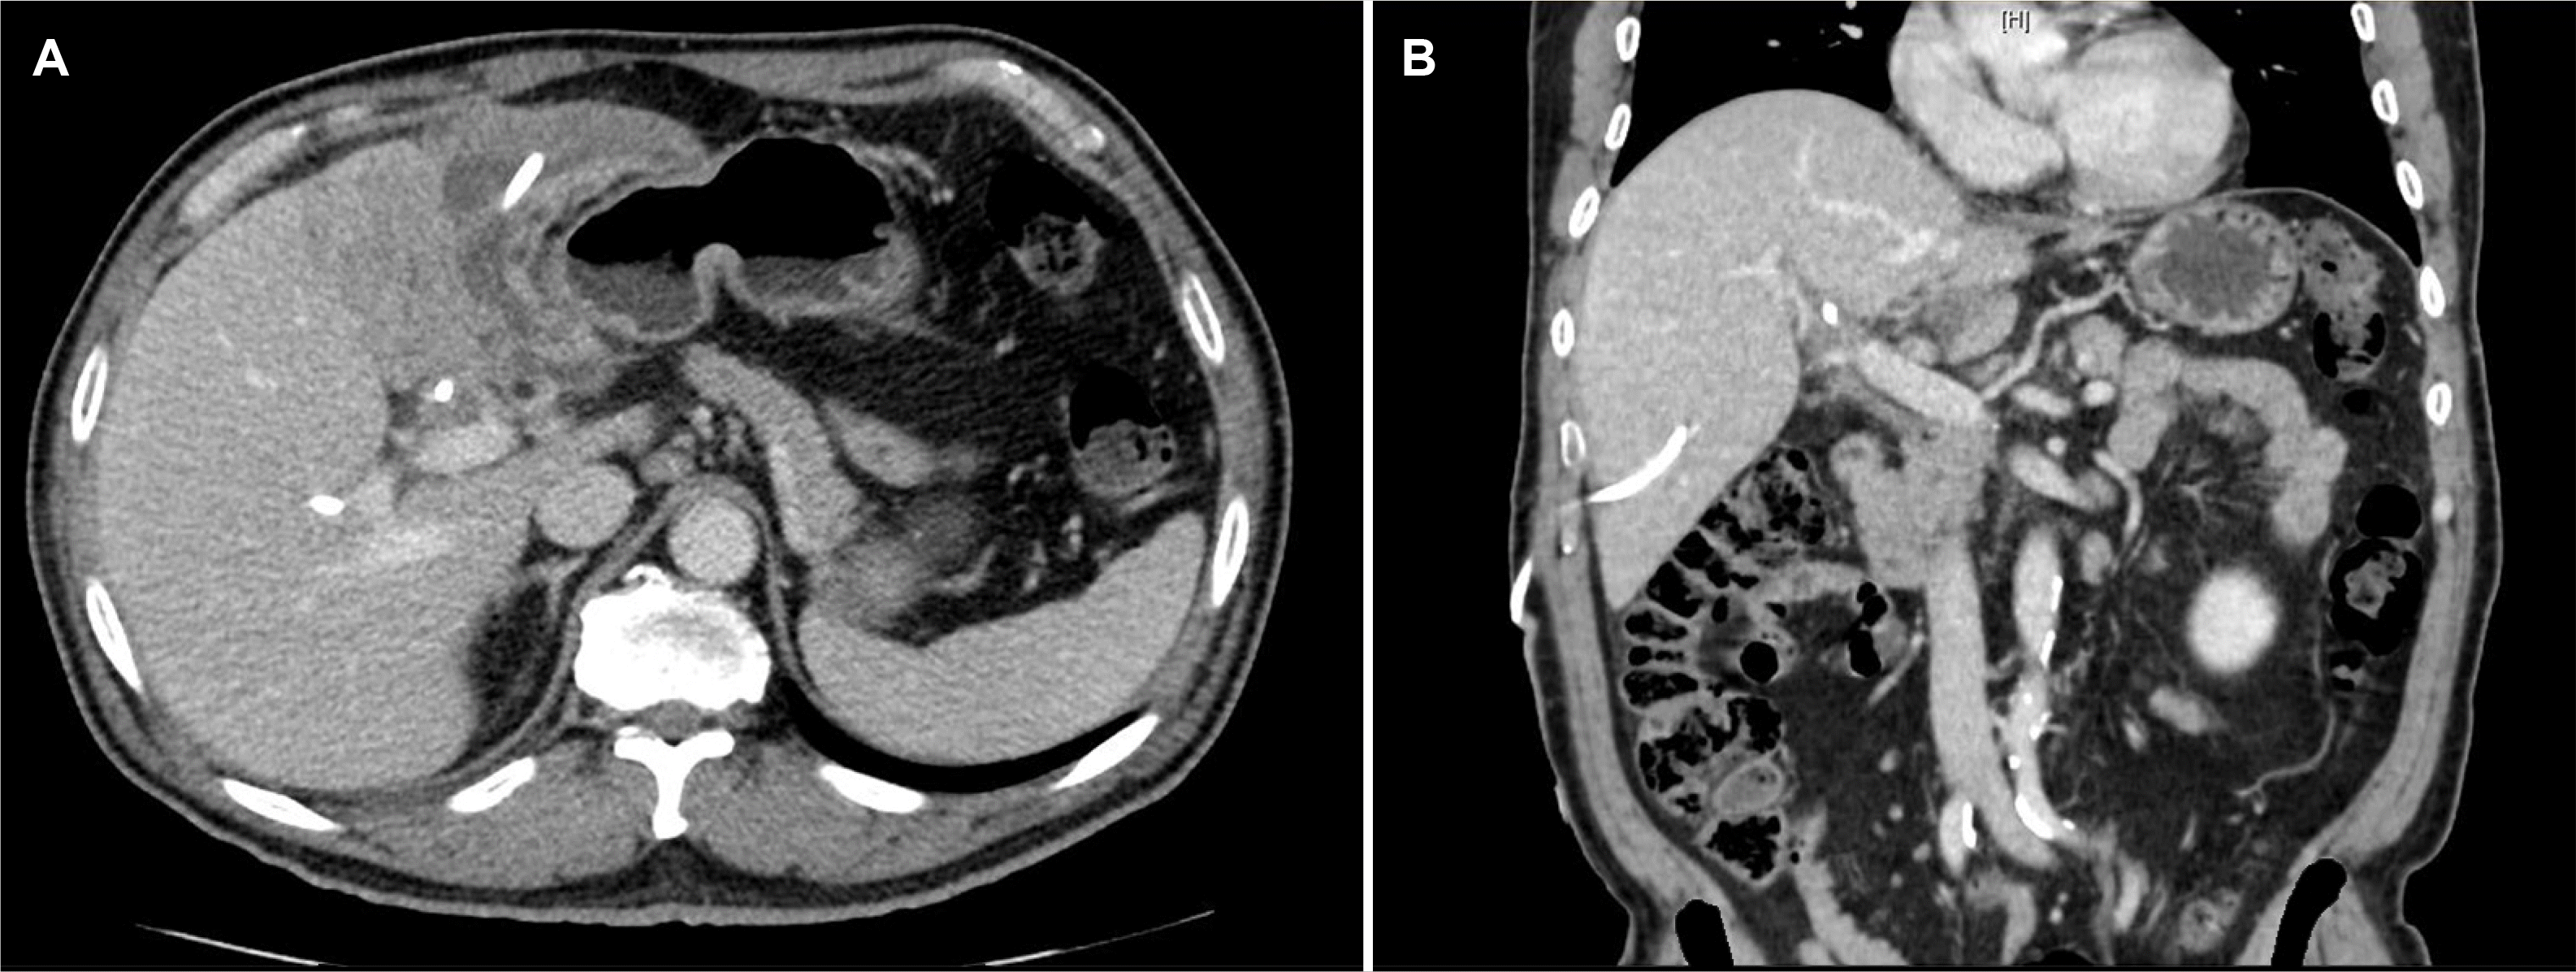

Fig. 2

(A) Probable 12 cm abscess in the left liver lobe. (B) Segmental enhancing wall thickening at the hilar bile duct resulting in upstream dilatation of intrahepatic ducts.

An abdominal ultrasound, which was performed initially, revealed a cystic lesion measuring 11 cm in length and a hypoechoic mass of 6 cm. No dilation of the common bile duct was observed (Fig. 1). An abdominal computed tomography (CT) scan revealed a lobulated cystic lesion exceeding 12 cm in size in the left lobe of the liver, characterized by thin rim enhancement and associated parenchymal shadowing changes, indicating a complicated cystic lesion (Fig. 2). Enhancing wall thickening was observed in the hilar bile duct, causing dilation of the intrahepatic bile ducts (Fig. 2B). Liver magnetic resonance imaging (MRI) revealed a 12 cm thick-walled cystic mass replacing much of the left lobe, with septations noted (Fig. 3A). Bilateral intrahepatic duct dilation was observed, predominantly affecting the left lobe (Fig. 3B). Based on the findings of a presumed abscess in the left lobe with bilateral intrahepatic duct dilation, the tumor markers were ordered, and a discussion was planned with the endoscopic retrograde cholangiopancreatography team regarding potential intervention. CA 19-9 was measured to evaluate the possibility of cholangiocarcinoma, yielding a result of 5.70 (reference range: 0–34), which was within the normal range. The initial diagnosis was a benign lesion, and despite the normal CA 19-9 levels, the possibility of a malignancy could not be completely ruled out. After consultation with the biliary team, the lesion suspected to be a common bile duct malignancy on MRI was considered more likely to be related to inflammation than a malignancy.

Abdominal contrast-enhanced CT revealed cyst wall thickening and high signal intensity on diffusion-weighted MRI, characteristic of a complicated hepatic cyst. These imaging features can make it difficult to differentiate from cholangiocarcinoma. On the other hand, the presence of a fluid–fluid level within the cyst, gas bubbles inside the cyst, or debris with a thick wall, typically associated with infection, are distinguishing features that help differentiate a complicated hepatic cyst from cholangiocarcinoma.4

The imaging characteristics that differentiate ICC from a liver abscess include a large, patchy necrotic area without enhancement in the mass, absence of the double target sign, rough and irregular inner wall and bile duct dilatation adjacent to the mass. Such imaging characteristics observed in a liver abscess highlight the need for careful imaging analysis to ensure an accurate diagnosis and appropriate treatment.12

In the present case, the imaging characteristics of the 12 cm-sized mass formation, irregular walls within the mass, and inner bile duct dilation observed around the mass warrant consideration of cholangiocarcinoma. On the other hand, cholangiocarcinoma can present atypically with multiple variable- sized hypodense masses with peripheral rim enhancement throughout the liver, necessitating a differential diagnosis from conditions such as echinococcal hepatic cysts or cystic metastases. In such cases, a tissue biopsy is essential for an accurate diagnosis.13 CA 19-9 and CEA are commonly used tumor markers to evaluate cholangiocarcinoma.1,14 In this case, the CA 19-9 levels were within the normal limits, which complicated the diagnosis. This underscores the importance of histological confirmation when the imaging findings are ambiguous.